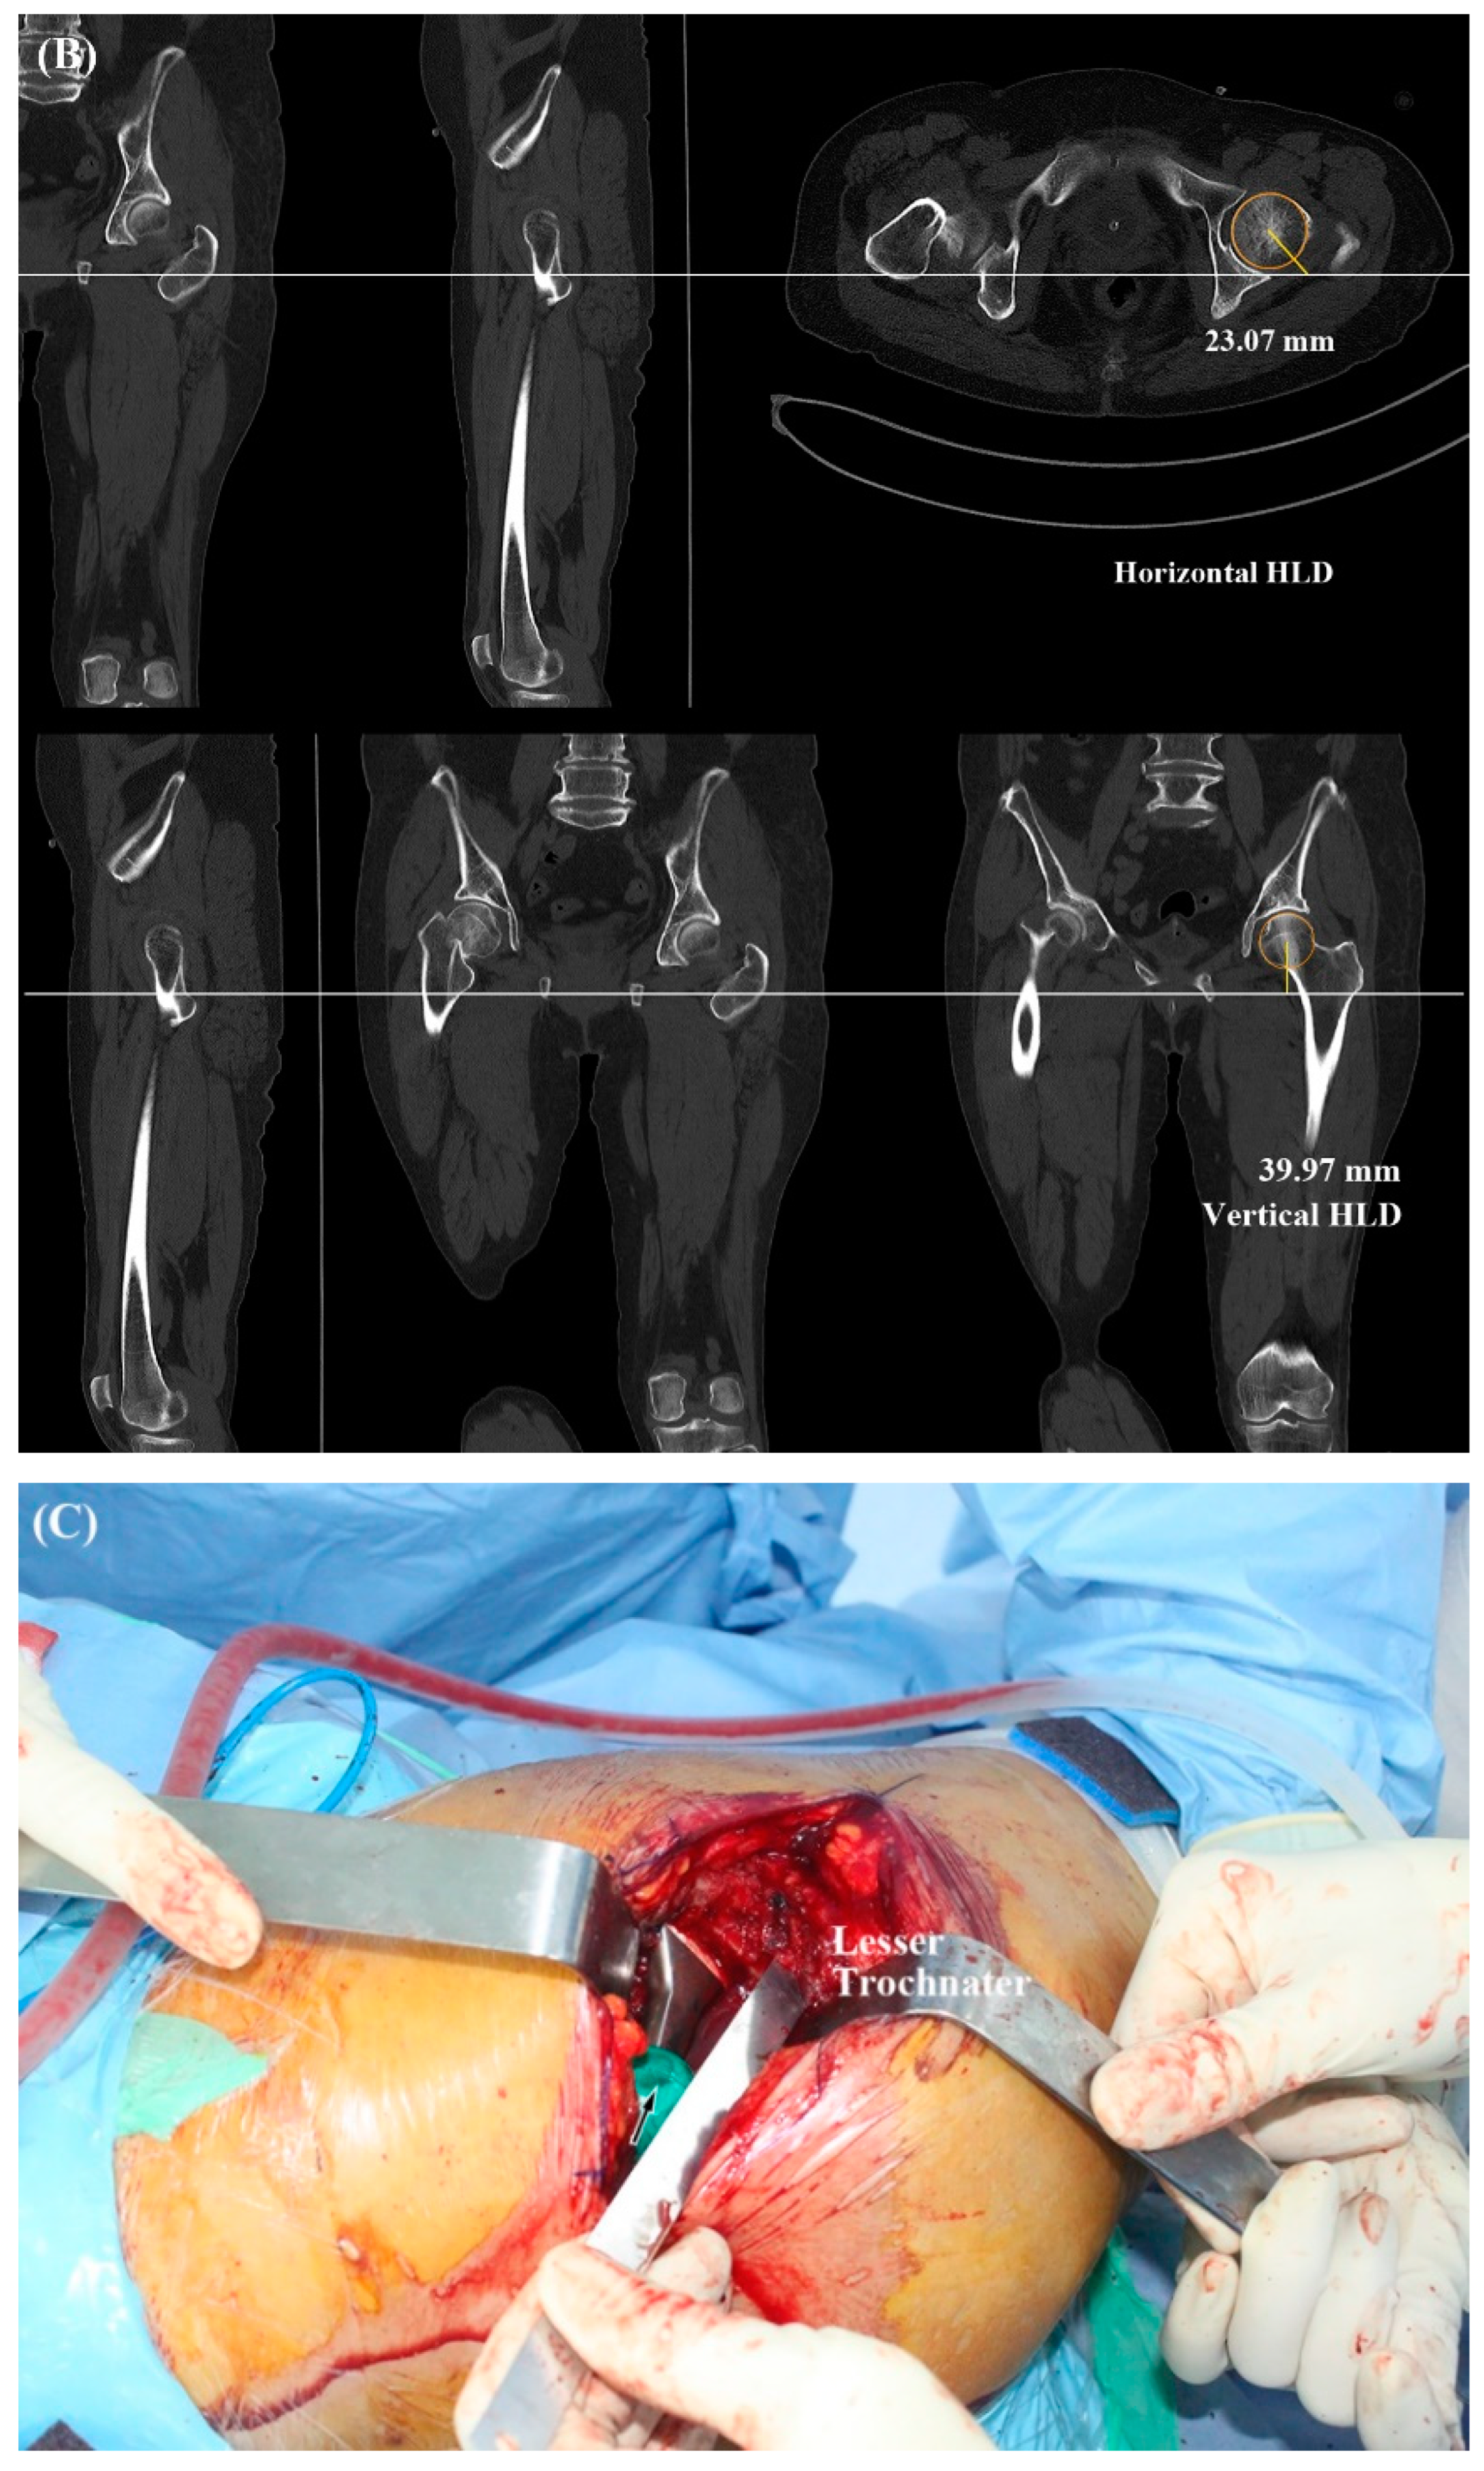

2.2. Radiologic Parameters

2.3. Operative Technique